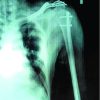

The procedure was performed in a beach chair position under general anesthesia and interscalene nerve block. The right lower extremities were separately cleaned and draped for graft harvesting. A 2.5 cm incision was made at the upper medial tibia, and the semitendinosus and gracilis tendons were harvested. A doubled semitendinosus-gracilis graft construct was prepared, measuring 7 × 220 mm with a width of 7 mm. After washing and layered closure of the incision, the right shoulder was prepped for surgery. The coracoid tip was identified, and skeletonization was performed using a 70°-scope system. Dissection of the coracoid was carried out, revealing an ununited fracture of the coracoid in longitudinal orientation along the length of the coracoid, representing a bony avulsion of coracoclavicular ligaments with superior displacement. The fracture site showed minimal mobility on probing. The fracture site was refreshed using an angled curette to promote healing. The intact portion of the coracoid base, located near the scapular neck, was identified. Using a tibial posterior cruciate ligament jig, through a 3 cm incision over the clavicle, serial drilling was performed from the clavicle to the coracoid over a guidewire using a 4.5 mm drill bit. Through a separate mid-rotator interval portal and an anterolateral portal, suture passage was performed. A dog-bone button construct with two suture tapes was fixed at the coracoid base and passed through the clavicular drill hole. The semitendinosus-gracilis tendon construct was then looped around the coracoid and secured anteriorly and posteriorly to the clavicle in a figure-of-eight configuration. After reducing the ACJ, the suture tapes were tied and trimmed, and a cortical button was placed over the clavicle. The tendon grafts were further tightened and sutured in place. Fluoroscopy confirmed acceptable reduction and stabilization of the ACJ. Using standard mid-rotator interval and anterolateral portals, along with a Wilmington portal, the labral repair was performed using three knotless suture anchors and suture tapes. Biceps long head tenodesis was completed in the groove using a separate knotless anchor and fiber wire sutures. At the end of the procedure, the ACJ and glenohumeral joints exhibited stability, and the biceps tenodesis remained intact. All surgical portals were closed in layers, and compression dressings were applied. The patient’s shoulder was protected in an arm sling pouch.(Fig. 3 )